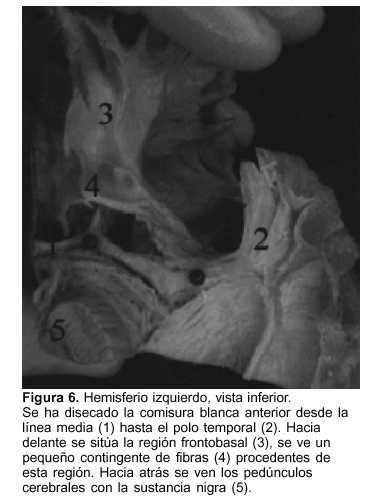

Hacia adelante y abajo, en la unión entre los surcos insulares anterior (SIA) e inferior (SII) se ubica el limen insulae(27). La disección de la corteza a este nivel permite ver los fascículos unciforme y occipitofrontal (este último más posterior). En profundidad con respecto a estos fascículos se sitúa la comisura blanca anterior. La misma puede ser disecada completamente, desde la línea media hasta el polo temporal, empleando la espátula de madera (figura 6).

Luego de la callosotomía se reseca hacia abajo y adelante la corteza orbitofrontal y la comisura blanca anterior. Dicha comisura conecta entre sí las regiones temporopolares y frontobasales(19,38-40). Este paso es importante en la técnica. Mittal y colaboradores(45) han visto una falla en el control de crisis en una paciente hemisferectomizada por displasia cortical extensa. La imagen por resonancia magnética (IRM) de control evidenció persistencia de corteza orbitofrontal y las crisis cedieron luego de la reoperación y resección de dicha región. Desde el punto de vista histológico el córtex orbitofrontal posterior se compone de mesocórtex y se conecta con el hemisferio contralateral a través del sector anterior de la comisura blanca anterior(19,38-40).